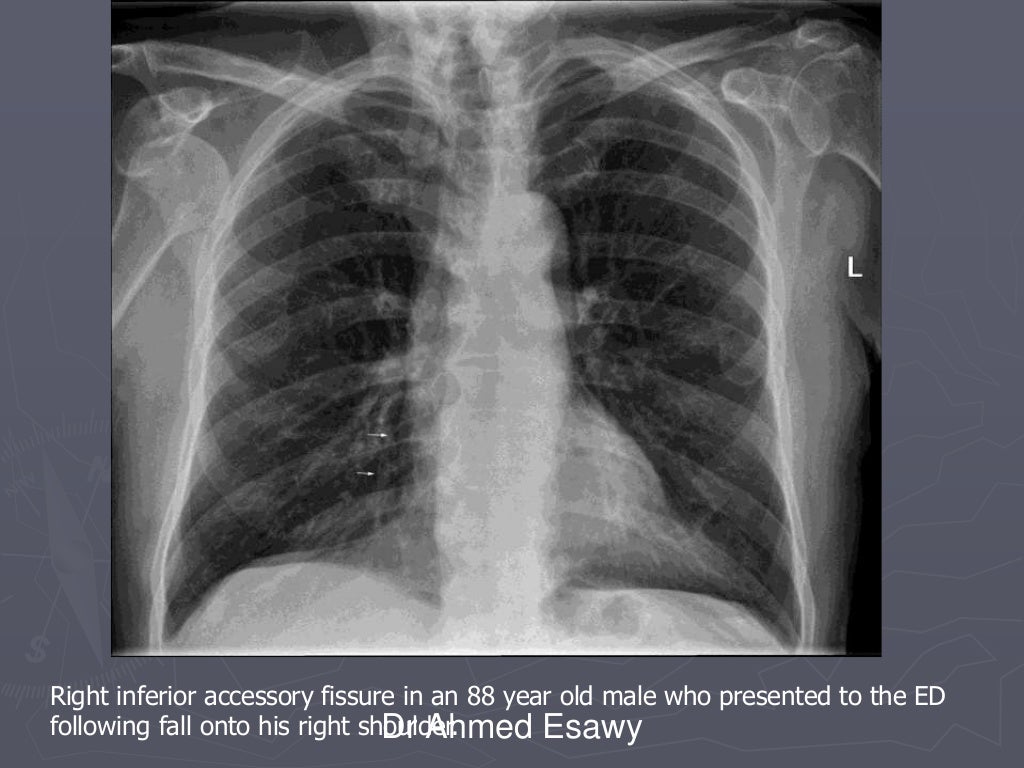

From www.slideshare.net

Linear lung density x ray Dr Ahmed Esawy What Is A Lung Density Lung nodules often are discovered. Nodules are areas that are denser than normal lung tissue and usually don't cause symptoms. Lung densitometry, namely measurement of lung density, is based on the property of the pulmonary tissue to variably. When it comes to any lung density, unfortunately, usually the first thought that creeps into the doctor's head is going to be. What Is A Lung Density.